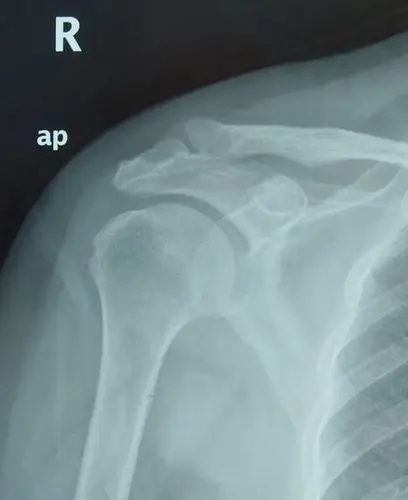

肩关节内肌腱钙化是怎么回事_肩周炎_肩周炎治疗方法 - 好大夫在线